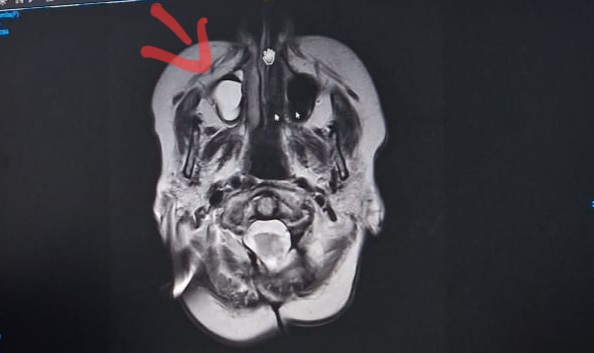

Die Ärzte sind sich nach wie vor uneinig. Die Stelle wo Anton sitzt, ist einfach zu ungünstig und eng um genau bestimmen zu können. 1 mm Wachstum sei wohl fast sicher. Aber eben nur fast. – Sie guckt mich an und fragt wie es mir wirklich geht?! Mit diesem Blick, der mir sagt „nun musst du dich wirklich nackig machen!

Aber, Moment, da ist noch etwas. Der Radiologe scheint seit 2020 etwas zu sehen. In meiner Kieferhöhle. Nur war es für meine Neurologin nie relevant. Eine Art Polype?

Scheint ziemlich groß zu sein. Auf meine Frage, ob diese Polype eventuell der Auslöser für den Nystagmus sein könnte kam ein deutliches „Nein“.